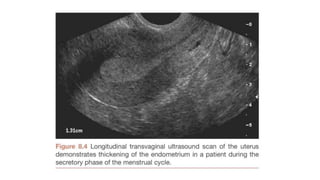

Ultrasound

- Second most common method of imaging

- Relies on high frequency sound waves generated by a transducer containing

piezoelectric material

- Principle : Generated sound waves are reflected by tissue interfaces and by

ascertaining the direction and time taken for a pulse to return it is possible to

form an image

Ultrasound - Second mostcommon method of imaging - Relies on high frequency sound waves generated by a transducer containing piezoelectric material - Principle : Generated sound waves are reflected by tissue interfaces and by ascertaining the direction and time taken for a pulse to return it is possible to form an image